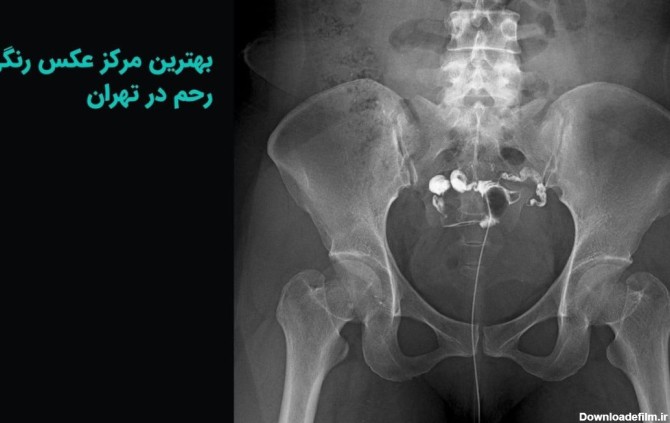

عکس رنگی رحم چیست؟ یک آزمایش اشعه ایکس که برای بررسی رحم و لوله های فالوپ و ناحیه اطراف آنها نگاه می کند و برای بررسی مشکلات ناباروری ممکن است انجام شود.

عکس رنگی رحم یا هیستروسالپنگوگرافی یکی از روش های تشخیصی شیوه ی تصویربرداری با اشعه ایکس است که معمولاً برای بررسی آناتومی رحم و لوله ها انجام میشود. عکس رحم

عکس رنگی رحم بدون درد؛ هیستروسالپنگوگرافی برای مشاهده داخل رحم و لوله های فالوپ استفاده می شود. می تواند نشان دهد که داخل رحم اندازه و شکل طبیعی دارد یا خیر.

عکس رنگی رحم برای بررسی مشکلات باروری در خانم ها انجام می شود. بهترین زمان انجام عکس رنگی رحم یک هفته بعد از پریود شماست. و نزدیکی قبل از عکس رنگی رحم باید محافظت شده باشد.